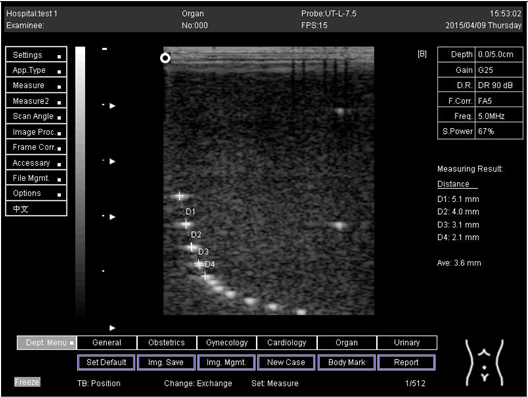

9.0 Axial resolution

Lateral resolution

Biomimetics 07 00130 i002

D1 = 5.0

D2 = 4.0

D3 = 3.0

D4 = 2.2

Biomimetics 07 00130 i009

D2 = 3.9

Biomimetics 07 00130 i010

D1 = 4.9

D2 = 4.1

D3 = 2.9

D4 = 2.0